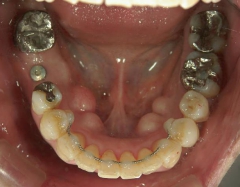

矯正歯科 治療前